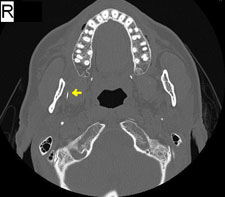

En cabinet, 2 aiguilles à gros calibre ont été utilisées comme points de référence pour le panorex (ill. 1). L'aiguille brisée a été localisée dans l'espace ptérygomandibulaire droit et on a tenté de l'extraire sous anesthésie locale. Après avoir essayé pendant 2 heures sans succès, il a été déterminé qu'il serait préférable d'extraire l'aiguille en salle d'opération. Huit jours plus tard, la patiente a été traitée dans la salle d'opération d'un hôpital local après avoir subi une tomodensitométrie (ill.2).

Ill. 2 : Tomodensitométrie (coupe axiale) montrant une partie de l'aiguille dans l'espace ptérygomandibulaire droit (flèche jaune).